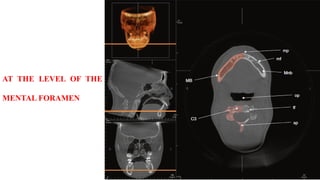

AT THE LEVEL OF THE

MENTAL FORAMEN

AT THE LEVELOF THE MENTAL FORAMEN